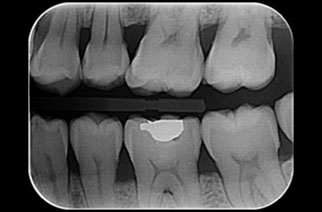

[ 拍摄咬翼 ]

为了更仔细确认牙齿头部拍摄X光片,

有效预防不能早期发现的牙齿面蛀牙 . -